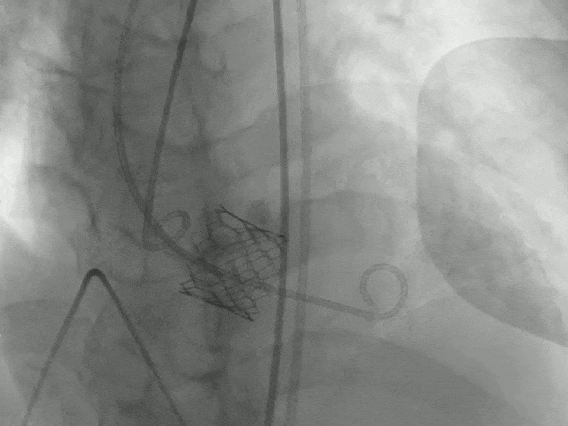

最关键的一步是输送瓣膜过弓。王奶奶的主动脉弓严重弯曲,团队凭借精湛的技术,让装载着瓣膜的输送系统顺利 「过弯」 并跨瓣。瓣膜定位后,医生精准释放了 23 mm 的人工瓣膜,在正确的位置安装好了新的 「心门」。

术后复查显示,瓣膜位置良好,没有明显瓣周漏。这下,王奶奶的心脏终于可以 「轻松呼吸」 了。